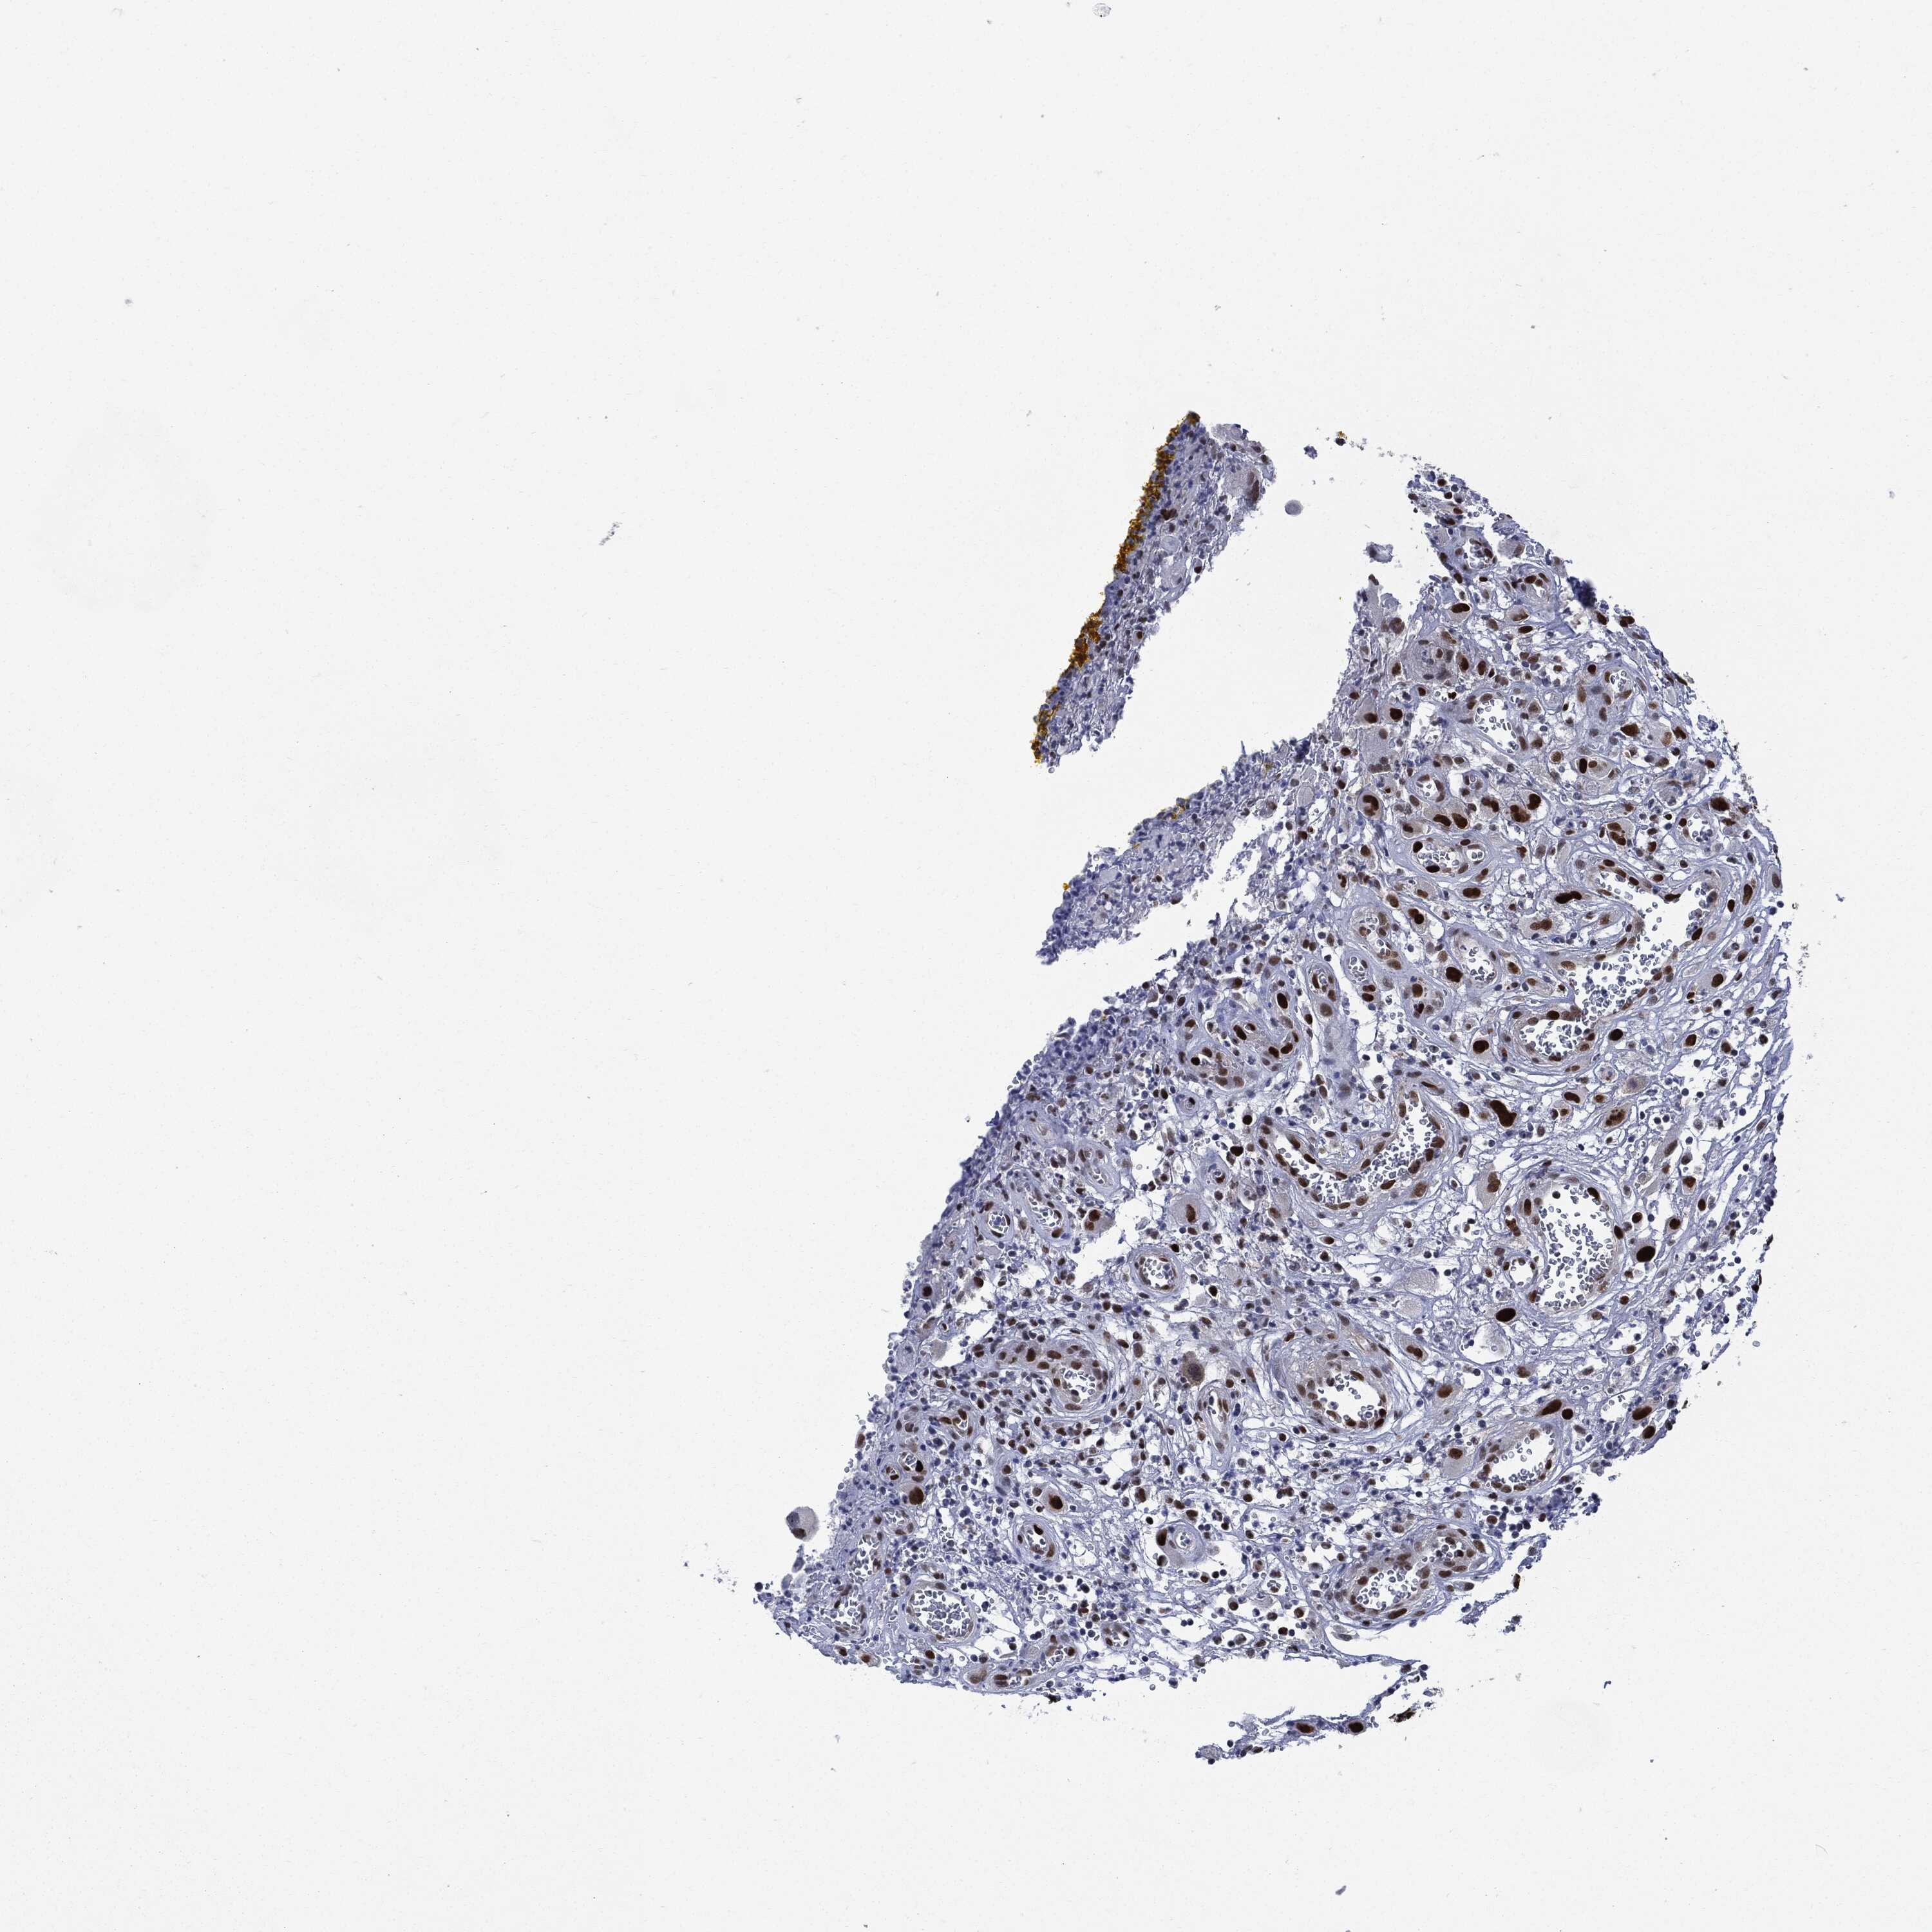

HEAD AND NECK CANCER - Protein expressioni

A mouse-over function shows sample information and annotation data. Click on an image to view it in a full screen mode. Samples can be filtered based on level of antibody staining by selecting one or several of the following categories: high, medium, low and not detected. The assay and annotation is described here.

Note that samples used for immunohistochemistry by the Human Protein Atlas do not correspond to samples in the TCGA dataset.

Antibody stainingi

Antibody staining in the annotated cell types in the current human tissue is reported as not detected, low, medium, or high, based on conventional immunohistochemistry profiling in selected tissues. This score is based on the combination of the staining intensity and fraction of stained cells.

Each image is clickable and will lead to virtual microscopy that enables deeper exploration of all samples and also displays staining intensity scores, fraction scores and subcellular localization as well as patient and tissue information for each sample.

HPA030521

HPA030522

HPA030523

CAB000148

CAB080240

CAB080241

CAB080242

Staining

High

Medium

Low

Not detected

Intensity

Strong

Moderate

Weak

Negative

Quantity

>75%

75%-25%

<25%

None

Location

Nuclear

Cytoplasmic/membranous

Cytoplasmic/membranous,nuclear

Squamous cell carcinoma, NOS

Squamous cell carcinoma, metastatic, NOS

Adenocarcinoma, NOS